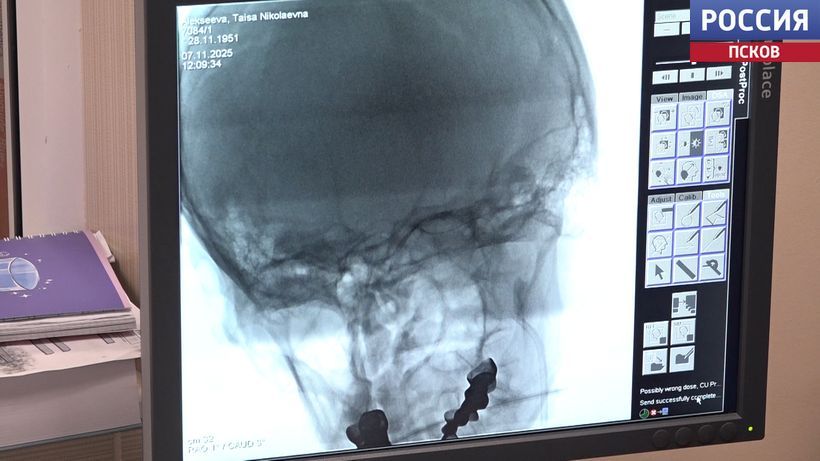

Оперативная медпомощь на высоком уровне. Так оценил работу Великолукского филиала областной больницы Сергей Леонов. Депутат Государственной Думы от фракции ЛДПР во время региональной недели посетил терапевтический корпус, где расположен региональный сосудистый центр. Репортаж Ларисы Чуриковой.